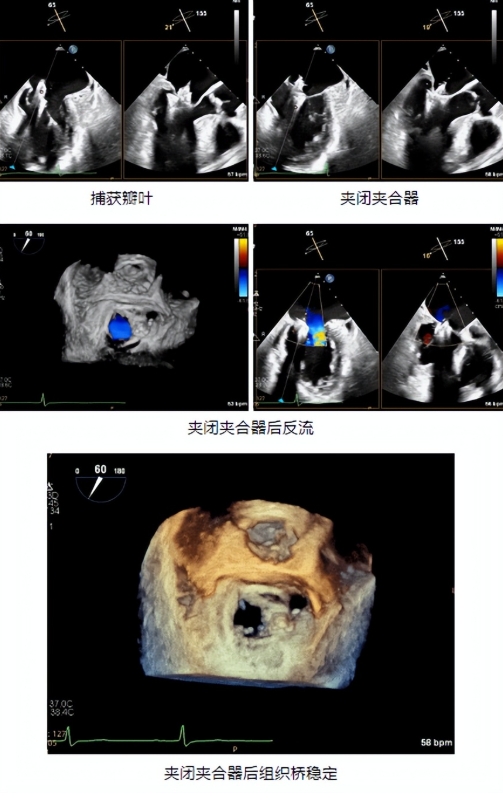

术中,专家团队在超声引导下,穿刺右侧股静脉-房间隔建立轨道,通过一根细长的输送导管,将夹合器送到患者心脏二尖瓣位置。经过精细调整,夹合器精准跨瓣定位到反流最严重的A2偏A3区,稳稳 “夹住” 脱垂的瓣叶,让原本松弛的“阀门”重新闭合。整个过程流畅高效,完全在超声引导下进行。术后即刻检查显示:二尖瓣反流从重度3+降到了轻微1+,“心门”对合良好,心脏泵血效率大幅提升,平均跨瓣压差仅1mmHg,手术圆满成功!术后患者恢复良好,胸闷憋气的症状彻底消失,已经能正常作息,不久后顺利出院,这场微创手术成功修复了老人的“心门”。